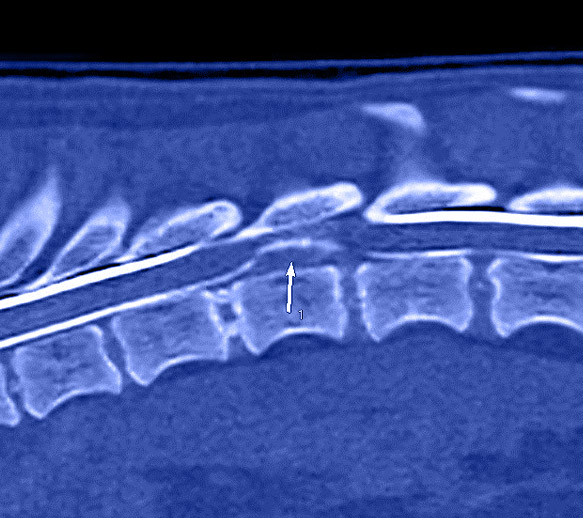

ci-contre : préparation d’une opération en urgence d’une hernie discale sur un petit chien paralysé

Nos vétérinaires chirurgiens ou spécialistes pratiquent la chirurgie neurologique (hernie discale, tumeur neurologique dont cérébrale, suture de nerf, malformation, tumeur vertébrale…).